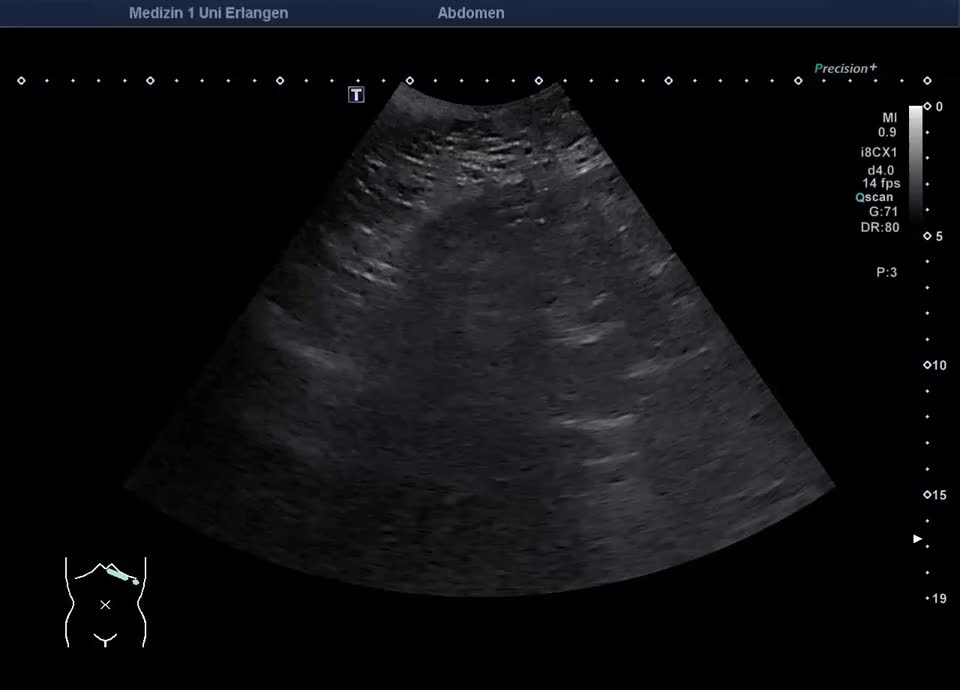

Normvariante: A. hepatica propria dorsal der Pfortader gelegen im proximalen Hilus (meist ist hier die A. hepatica zwischen DHC und Pfortader zu finden)